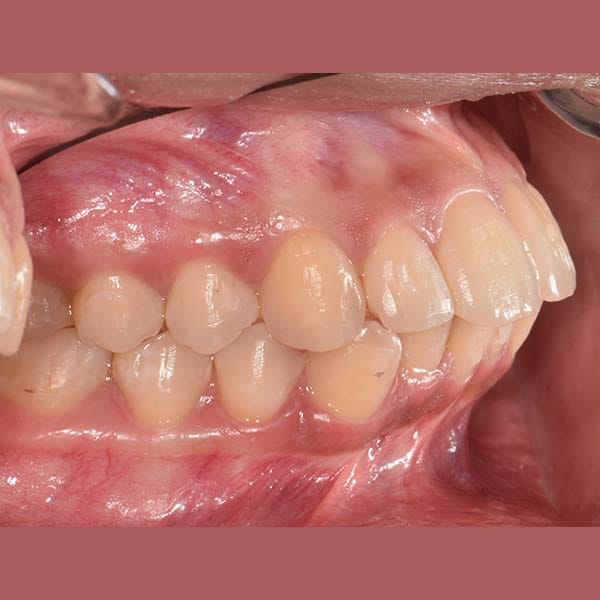

راجعتني هذه الآنسة الشابة وهي تشكو من بروز أسنانها الأمامية في كلا الفكين العلوي والسفلي، وهي حالة نسميها عادةً “البروز المضاعف”.

بعد الفحص، أكد الدكتور خالد الكاتب أن البروز كان كبيراً، وفي معظم هذه الحالات، يكون الحل الأمثل هو قلع بعض الأسنان لتوفير مسافة. وبالفعل، اعتمدت خطة العلاج على قلع الضواحك العلوية والسفلية. تم بعد ذلك استخدام تقويم الأسنان لاستغلال هذه الفراغات في إرجاع الأسنان الأمامية للخلف وتعديل ميلانها.

كما تظهر الصور، تم تصحيح البروز المضاعف بشكل كامل. تراجعت الأسنان الأمامية في كلا الفكين إلى وضعها المثالي، مما أدى إلى تحسين كبير في المظهر الجانبي للوجه وابتسامة أكثر جمالاً وتوازناً. في النهاية، بات بإمكان مراجعتنا الابتسام بثقة مجدداً.